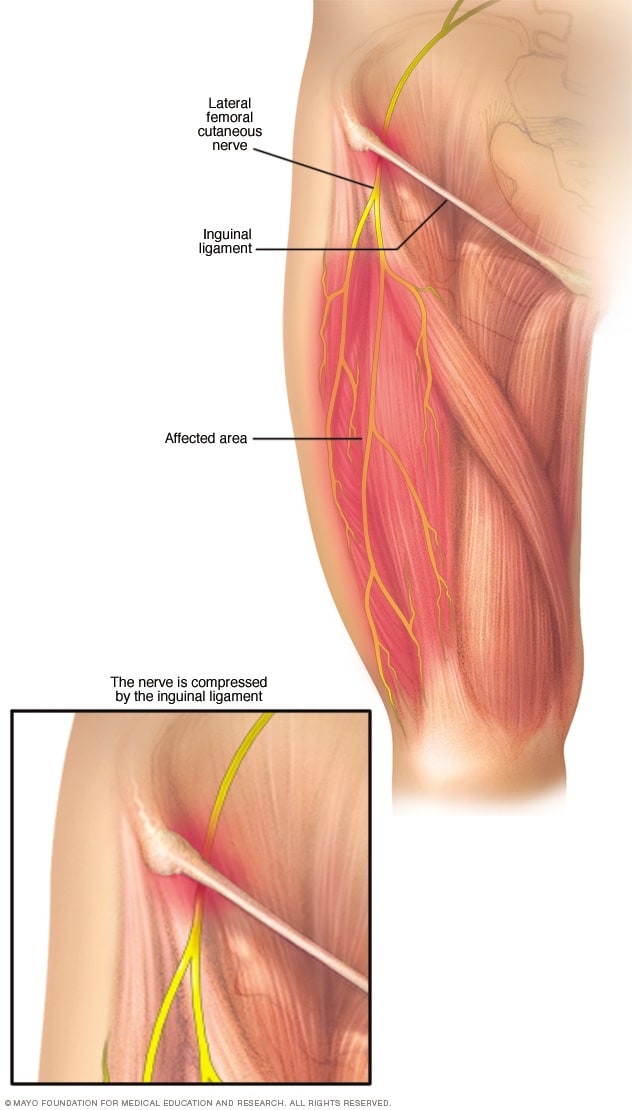

Meralgia paresthetica Symptoms and causes Mayo Clinic

Product Name: Muscle on outside of clearance thighMuscle Strains in the Thigh Florida Orthopaedic Institute clearance, Lateral leg pain more than just the IT Band Revo Physiotherapy clearance, 6 Power Packed Outer Thigh Exercises For Lower Body Strength DMoose clearance, 10 Best Thigh Exercises For Leg Day Workouts Steel Supplements clearance, Diagnosing Lateral Thigh Pain IT band syndrome Hip Bursitis and clearance, Can Rolling Your IT Band Make It Worse Functional Performance clearance, Thigh muscles side view Human anatomy Leg anatomy Human muscle clearance, Quad Muscles Function and Anatomy clearance, Rolling of the IT band anatomy of outer thigh muscles blog post clearance, Vivian Grisogono ABOUT THE FRONT THIGH MUSCLES clearance, Iliotibial band syndrome ITBS clearance, Adductor muscles of the hip Wikipedia clearance, The Secret to Resolving IT Band Syndrome using Thai Massage Thai clearance, Professor Ernest Schilders The London Hip Arthroscopy Centre clearance, Muscles of the Posterior Thigh Hamstrings Damage TeachMeAnatomy clearance, Runners Knee also known as ITB Syndrome Do You Have It and How clearance, The Physio Detective The ITB 5 things you probably haven t clearance, Diagnosing Lateral Thigh Pain IT band syndrome Hip Bursitis and clearance, Vivian Grisogono ABOUT THE FRONT THIGH MUSCLES clearance, Anatomy Of Human Thigh Muscles Greeting Card clearance, Muscles of the Human Body clearance, Understanding Iliotibial Band Syndrome Saint Luke s Health System clearance, Diagnosing Lateral Thigh Pain IT band syndrome Hip Bursitis and clearance, Meralgia paresthetica Symptoms and causes Mayo Clinic clearance, Foam rolling IT band Dos and don ts clearance, What is the Vastus Lateralis Muscle Orchard Health Clinic clearance, What is the muscle on the back of your thigh Quora clearance, IT band Friction Syndrome Ortho Rhode Island clearance, Why does the top of my left thigh ache when raising it up Quora clearance, Anatomy of Leg Muscles Plus How to Make the Most of Leg Exercises clearance, Meralgia Paresthetica Neuromuscular and Electrodiagnostic Clinic clearance, Soft Tissue Reconstruction of the Lateral Thigh and Hip SpringerLink clearance, Why Is Your Thigh In Pain 6 Common Causes Carex clearance, Anatomy of the Hamstring Upper Leg clearance, Muscle Knots in Side of Leg IT Band Tiger Tail USA clearance, Front Thigh Pain Anterior Thigh Pain Symptoms Causes Treatment clearance, Pelvic hip and thigh muscles of the right side of the body Part clearance, Outer Quad Exercises 7 Must Do Exercises Fitbod clearance, The Hip Abductor Muscles Trochanteric Bursa and Lateral Outside clearance, Muscles of the hips and thighs Human Anatomy and Physiology Lab clearance, Anatomy of the Piriformis Muscle Spine health clearance, Why Does The Outside Of My Hip Hurt What to Do About It clearance, Vastus lateralis muscle Wikipedia clearance, What is IT Band Syndrome and How Can I Fix It clearance, IONA Physiotherapy WHAT AND WHERE IS THE ILIOTIBIAL BAND ITB clearance, Groin Strain Symptoms Causes Treatment Rehabilitation Exercises clearance, Simple Ways to Stretch Your Outer Thighs 9 Steps with Pictures clearance, Meralgia Paresthetica Causes Symptoms Treatment clearance, Knee Muscles Anatomy Function Injuries Knee Pain Explained clearance, How to Cure Thigh Muscle Pain clearance.